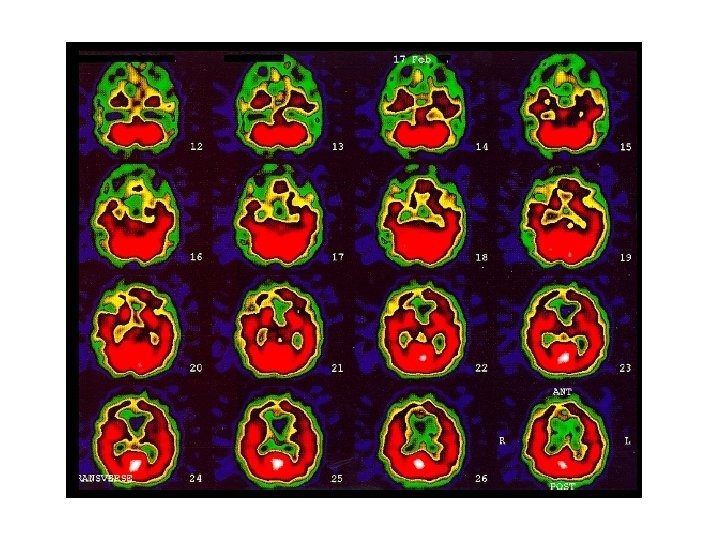

Normal SPECT brain scan § The mid trans-axial scans (6 images) is divided into 3 parts: frontal, temoro-parietal and parieto-occipital on either side of cerebral hemisphere. +3 lower trans-axial cerebellar sections are compared as regards visual tracer intensity (color) and quantitatively by count intensity. § Cerebellar counts and tracer intensity is the reference region? Usually spared in most diseases. § Rt: Lt regional count should be within 1 -+5% , >5% is abnormal. § Coronal views are useful in temporal lobes lesions. § normally, gray and white matter are easily recognised, higher counts at BG, thalami, visual cortex, and cerebellum.